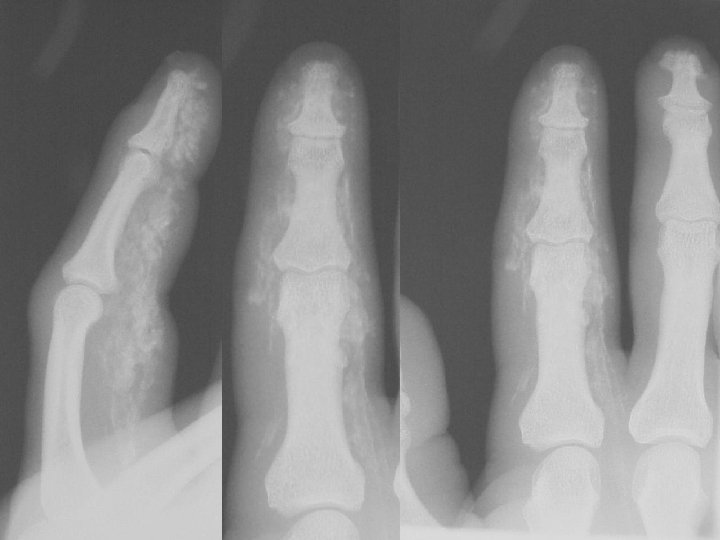

Scleroderma • Hands and pressure areas • Acro-osteolysis • Soft tissue changes • Subluxations

Calcification By site Finger Tips • • Scleroderma CREST Dermatomyositis Trauma

Calcification By site Articular cartilage • Osteoarthrosis • • CPPD HADD Hyperparathyroidism Haemochromatosis